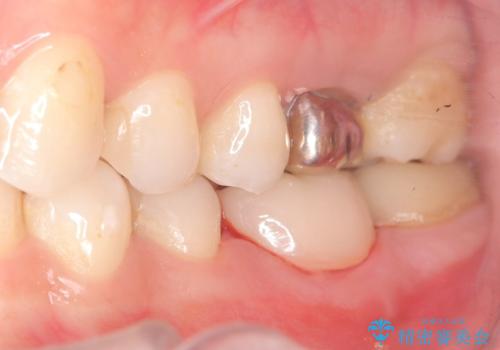

保存が難しい左下6番目の歯を抜歯し、左下8番目の歯(親知らず)を抜歯窩に移植しました。歯牙移植後の動揺防止のため暫間固定を行っています。

また移植後2週間経過時点で根管処置が必要となります。

骨との定着を確認し、今後矯正治療を行う予定のためレジン冠をセットしています。